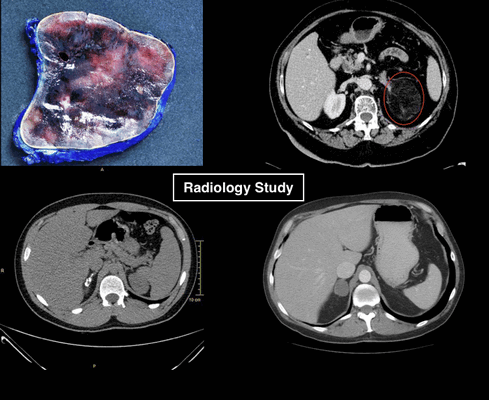

В верхнем ряду представлены изображения изменения размеров аденомы на фоне лечения. Обратите внимание, как производится измерение данной функционирующей аденомы.

- Следовательно характеризуем данное образование, как

- Стабильное в размерах в течение года и более образование.

- NB! образование должно быть измерено одним и тем же специалистом.

- Сравнение по описанию само собой не допускается!

- Рекомендуем биохимические исследование и консультацию эндокринолога.

В нижнем ряду представлены изображения пациента с верифицированной карциномой надпочечника. Данному пациенту был назначен КТ контроль через год, но не были рекомендованы консультация эндокринолога и биохимические исследования. При КТ контроле через 9 месяцев образование существенно увеличилось в размерах.